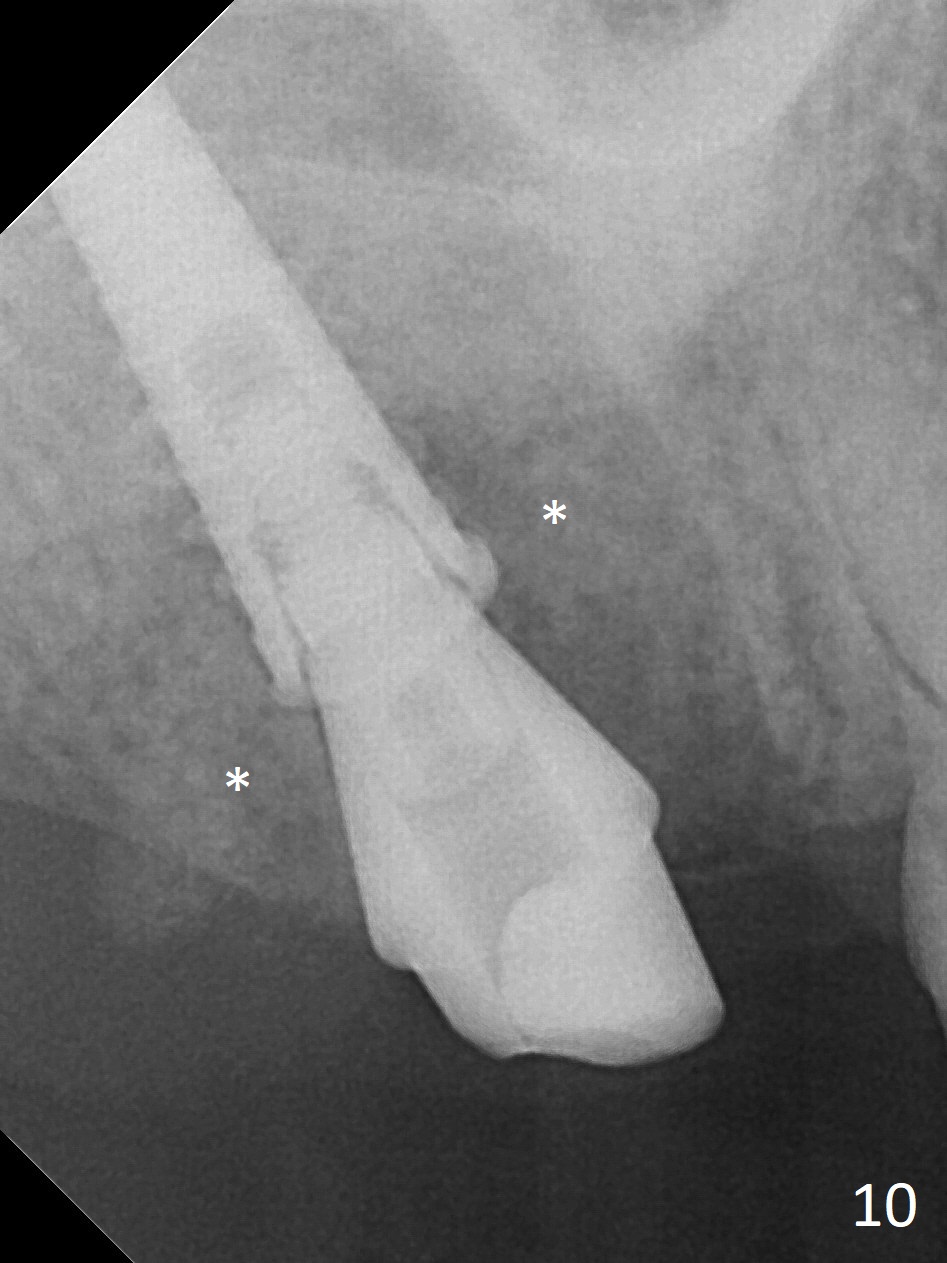

There is a fistula distal to the tooth #2 with deep pocket distopalatally (Fig.1 *), corresponding to palatal root fracture (Fig.2). There is a septum (Fig.3 S) between the buccal (B) and palatal (P) sockets. Osteotomy is initiated in the center of the septum (Fig.4 black circle). In fact the center of the socket is buccal (red circle), in which osteotomy should have been established because of the presence of the distopalatal bony defect associated with the root fracture and the distal fistula. The less ideal initial osteotomy leads to palatal placement of the implant and abutment (Fig.11 vs. 12).

Fig.5 shows the mesial slope of the socket (M), which is more or less the center of the socket mesiodistally. If the osteotomy were set up in the red circle (Fig.6) in the mesial slope (Fig.8 green dashed line), the trajectory of 4.5x11 mm dummy implant (Fig.7) would be more ideal (Fig.8 red outline) with more native bone contact. Finally a longer IBS implant is placed (4.5x15 mm, Fig.9,10) to achieve primary stability (50 Ncm). When the provisional is removed for impression 3 months 10 days postop, the implant is found to have been placed distopalatally (Fig.13), which should have been avoided. It appears essential to use guide for a distal implant. It is agonizing to re-encounter the off-axial implant (Fig.14) and the distopalatal access hole (Fig.15) 1 year post cementation. It is also amazing that the abutment screw has not loosened. A fair-sized piece of bone graft has just been removed buccally (Fig.15,16). The patient complains of sensitivity 2 years 3 months post cementation, although there is no abnormality around the implant crown. Guided surgery is essential to avoid restoration complication. There is no thread exposure nearly 3 years post cementation; in fact the apical portion of the abutment is covered by the bone (Fig.17,18).